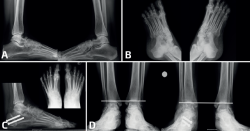

Figura 2. Paciente que consultó por dolor en la primera metatarsofalángica después de una artroplastia del dedo gordo. De manera incidental, al hacer radiografías en proyección dorsoplantar en carga (A) se observó una coalición talonavicular en el pie derecho que era asintomática. La coalición se apreciaba también en las proyecciones oblicua (B) y lateral (C). En las radiografías anteroposteriores de ambos tobillos en carga (D) se aprecia el valgo del pie derecho, algo que era también visible en una foto clínica (E).

- Talonavicular: la mayoría de las coaliciones talonaviculares son congénitas, con herencia autosómica dominante, pero en algunos casos pueden formarse durante la preadolescencia(16). En el estudio radiológico es característico el “signo de la seta”, visible en las radiografías en carga en proyección dorsoplantar, donde los contornos de la fusión ósea remedan la forma de un hongo(14) (Figura 2). Es frecuente la existencia de este tipo de coalición en síndromes malformativos como el de Nievergelt-Pearlman(17). Cuando una coalición talonavicular es sintomática, suele serlo de manera leve, con molestia más que dolor(18,19,20,21,22). En la mayoría de los casos el tratamiento conservador suele ser suficiente para mejorar la sintomatología(23,24). Cuando es necesaria una cirugía, suele realizarse una corrección de la deformidad con una osteotomía(25).